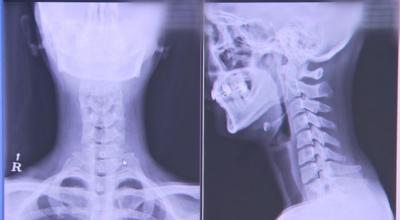

외부로부터 강력한 충격은 주로 교통사고로 인해서 발생돼요. 교통사고만 나면 주로 목을 잡게 되죠? 뒤차에 받혔을 때 주로 경추에 충격을 주어 주로 경추염좌 진단을 받는데 가벼운 증상일 때 빨리 치료를 해야 되므로 입원해서 치료를 받는게 좋아요. 퇴형성으로 목 디스크 증상이 조금씩은 다 있는데 이럴 때 교통사고 나면 병원 가서 X-Ray 촬영하면 디스크(경주 염좌) 진단을 받게 됩니다.

목디스크 증상이 나타날때 빨리 발견하여 비수술 치료를 받고 꾸준히 관리하는 것이 베스트이죠. 목디스크 환자 중 수술을 진행하는 환자는 2% 미만으로 현저히 적다고 해요. 수술을 진행하는 경우는 감각이 느껴지지 않는 마미증후군이나, 한쪽 다리가 눈에 띌 정도로 야윈 경우에만 진행하므로 올바른 자세 교정만으로도 충분히 호전될 수 있는 질병이죠. 목에 연관된 검사는 MRI나 CT를 이용해요. 그러나 전자의 경우 비용이 굉장히 비싸기 때문에 디스크 증세가 확실하다고 생각될 경우에만 선택적으로 하고 의무적으로 하는 건 아니니까 비용에 대해선 부담을 가지지 마시길 바래요.